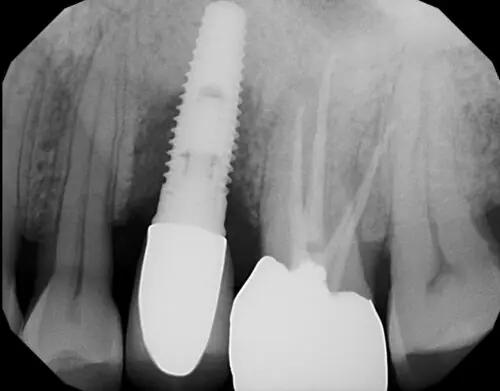

Діагностика

Пацієнтів з ознаками відторгнення імплантату ретельно обстежують.

Проводиться:

- оцінка стану ясен;

- перевірка на наявність запалення, набряку та кольору слизової оболонки;

- оцінка стану кісткових тканин візуально та за допомогою обладнання;

- визначення рухливості імплантату;

- перевірка на наявність або відсутність гною навколо шийки та тіла імплантату;

- пальпація підщелепних лімфатичних вузлів, які можуть бути збільшені за наявності інфекції.

На основі результатів діагностики визначається точна причина болю та запалення, а також розробляється план лікування.